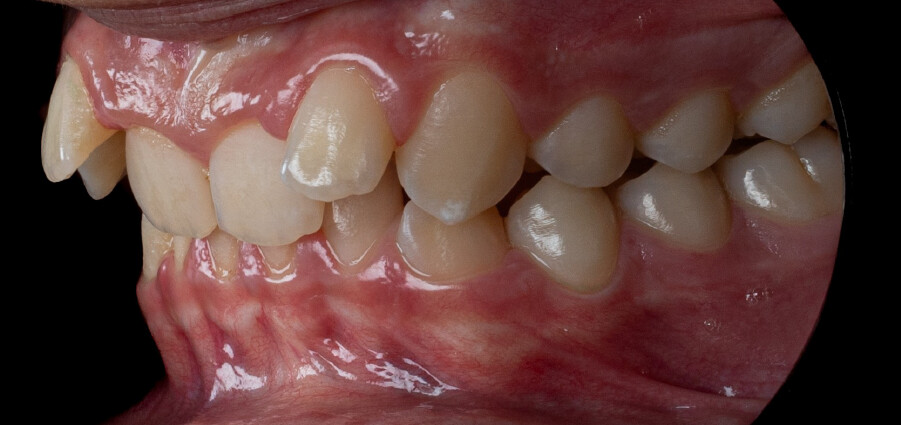

A 13-year-old male patient presented with a deep bite, characterized by near-complete coverage of the mandibular incisors. Clinical evaluation revealed bi-arch crowding, dental rotations, and proclination of the maxillary lateral incisors, contributing to the patient’s esthetic concerns. The facial profile was retrusive, consistent with mandibular retrognathism, and no significant periodontal abnormalities were detected.

The patient presented with a skeletal Class II relationship with bilateral molar and canine Class II and a Class II division 2 dental pattern. The deep bite was associated with anteroinferior crowding and an accentuated Curve of Spee. Facial analysis revealed good symmetry, a slightly increased lower facial third, and a convex profile characterized by mandibular and chin retrusion. Lip competence was mildly reduced, with a decreased nasolabial angle and mentalis hyperactivity, all of which compromised overall facial harmony.